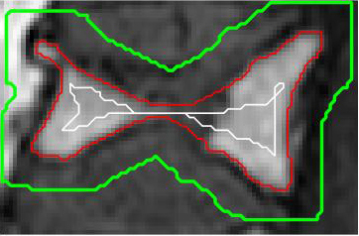

The balance induced by the weights produces smoother borders at regions with small pixel intensities. Moreover, as long as the interior annotation contains small portions of the dark and bright regions, it can work well even with rough interior and exterior seed points. To better illustrate this, Figure 3 shows a few iterations of BGrowth for a single vertebral body segmentation. Note that, at iteration 5, a few dark regions (outside of the vertebral body) are still part of the foreground and, as the balancing goes on, the foreground shrinks towards the ground-truth. The final result is quite close to the manual segmentation. Figure 4 shows another example of BGrowth’s iterations on five lumbar vertebrae. Note that, the method works quite well even when a simple line is given as seed points. The only constraint is that the interior annotation has to comprise the dark/bright regions within the vertebral body.

As we work with the balance of old and new strength factors, it might happen that the process of expansion goes back and forth on the same pixel. Therefore, we would recommend the definition of a maximum number of iterations depending on the kind of image being segmented. We have empirically used a maximum of 30 iterations for the segmentation of a single vertebral body. For a whole exam, as exemplified in Figure 4, a few more iterations might be necessary.